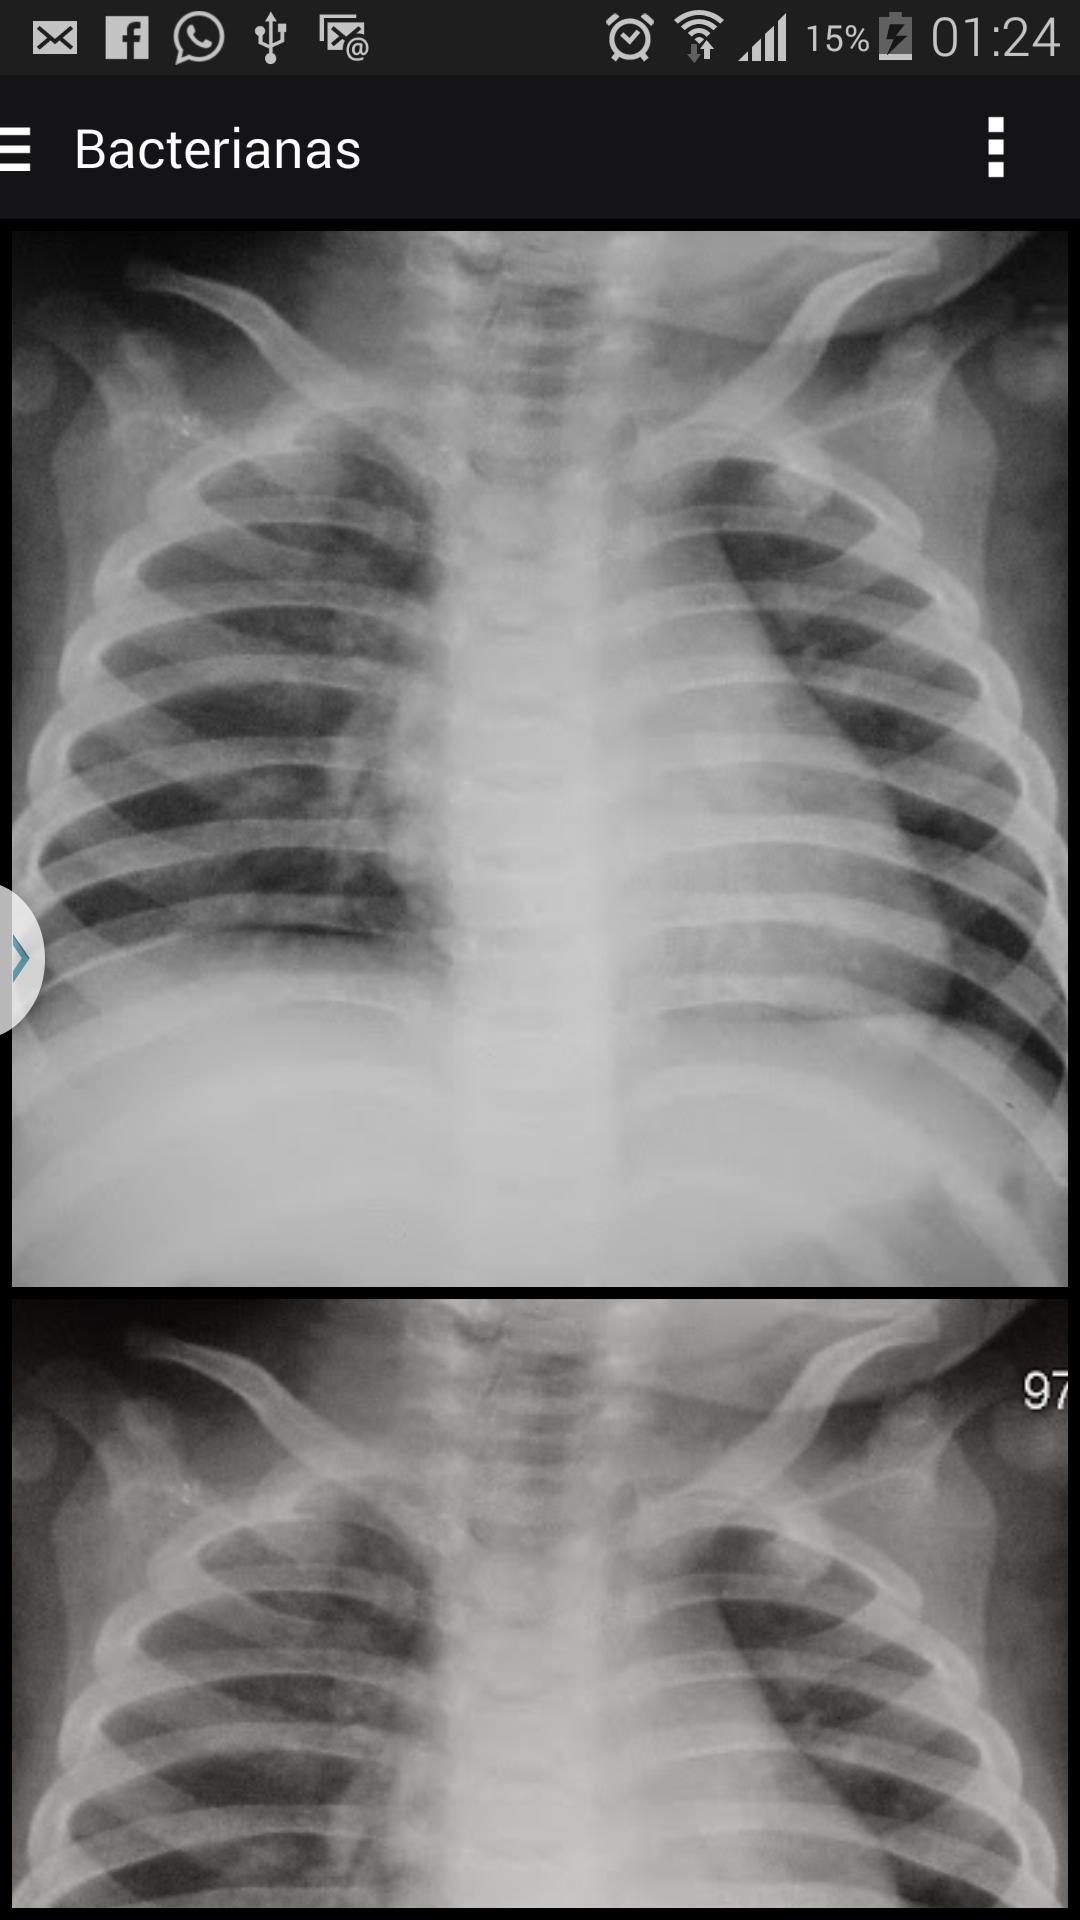

어린이의 폐렴 진단을 지원하기위한 X- 레이 이미지

흉부 X- 레이는 세계 보건기구 (WHO)에 의해 매일 임상 실습에서 폐렴 진단에 현재 이용 가능한 최상의 방법으로 간주됩니다. 그러나 관측 변동에 대한 연구는 모든 의학 분야에서 일반적이지만, 이미지 연구에서 우세합니다.이 분야에서 관찰자의 성능은 지난 10 년 동안 얻은 기술 발전과 대조되는 연약한 부분을 나타냅니다.

진단 테스트의 평가에서 기본 요소. 흉부 방사선 진단의 경우, 특히 어린 시절의 정확도는 상호 및 관찰 내 계약을 통해 주관적으로 평가됩니다. 교수 진단에서 참조 (표준)로 사용될 수있는 패턴은 거의 없기 때문입니다.